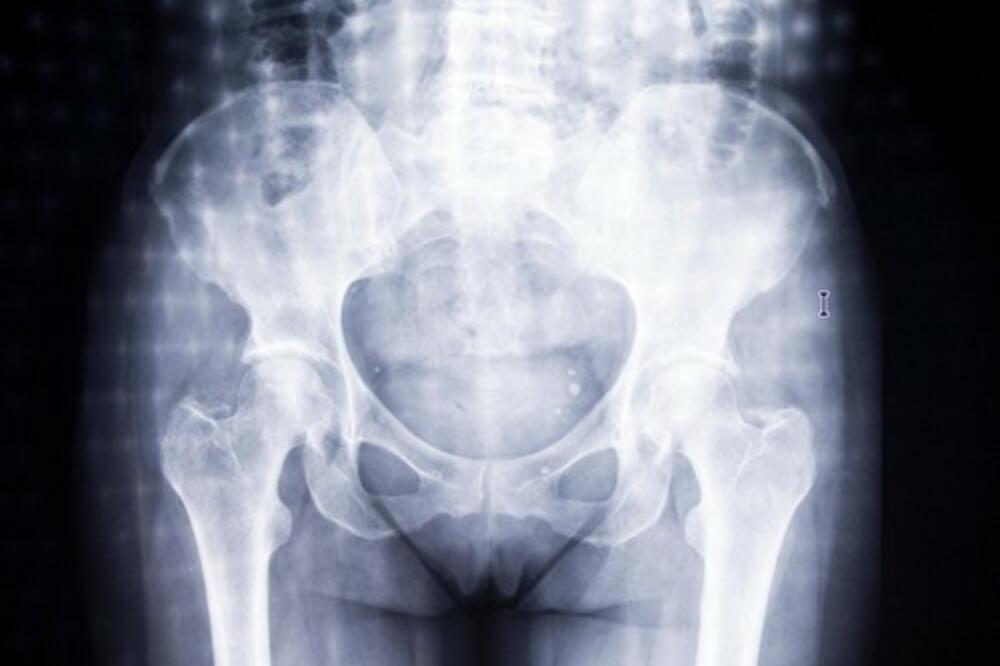

Od žena koje sve jedu, do onih koje konzumiraju samo ribu ili onih kojima je meso povremeno na meniju, vegetarijanke su bile jedina grupa sa povećanim rizikom od preloma kuka.

Vegetarijanke, žene koje su izbacile meso iz svoje ishrane ili ga nikada nisu ni jele, imaju 33 odsto veći rizik od preloma kuka u poređenju sa onima koje konzumiraju meso, otkrila je studija naučnika sa University of Leeds, sprovedena na više od 26.000 žena srednjih godina u Velikoj Britaniji.

Među 26.318 žena, koje su u vreme kada su odabarane za studiju bile u dobi od 35 do 69 godina, 822 slučaja preloma kuka su primećena tokom 20 godina studija – što je predstavljalo nešto više od 3 odsto populacije posmatranog uzorka. Nakon prilagođavanja faktorima kao što su pušenje i godine starosti, vegetarijanke su bile jedina grupa sa povećanim rizikom od preloma kuka. Ova studija je jedna od retkih koja upoređuje rizik od preloma kuka kod vegetarijanaca i mesojeda gde je pojava preloma kuka potvrđena na osnovu bolničke dokumentacije. Naučnici naglašavaju da postoji potreba za dodatnim istraživanjem tačnih uzroka zašto su vegetarijanke u većem riziku od preloma kuka.